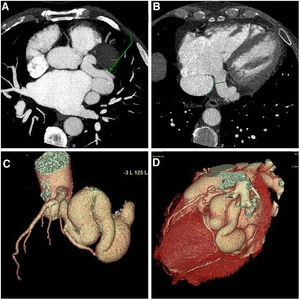

- Pulmonary atresia with intact ventricular septum

- Alejandro Fernández-Cisneros, Bosco A. Moscoso, Stefano Congiu

- Rev Esp Cardiol. 2025;78:1020-1